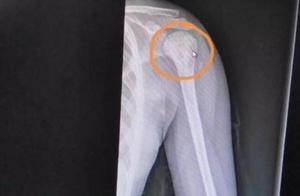

April 2019, my within an inch of confused a road in the village in city of Guangzhou white pond. Because border Guangzhou southern hospital, the serious illness ill patient that before the village in white pond city collected a large number of each district, will demand medical service. Cross narrow street alley, I walk into a dim a house owned by a citizen, the cancer boy that saw this 13 years old in the rented house -- Zhang Jia hopes. Be afraid that the village in the city that differs in dirty chaos is affected by the bacterium, he is wearing guaze mask all the time, more appear sallow and emaciated. April 2019, my within an inch of confused a road in the village in city of Guangzhou white pond. Because border Guangzhou southern hospital, the serious illness ill patient that before the village in white pond city collected a large number of each district, will demand medical service. Cross narrow street alley, I walk into a dim a house owned by a citizen, the cancer boy that saw this 13 years old in the rented house -- Zhang Jia hopes. Be afraid that the village in the city that differs in dirty chaos is affected by the bacterium, he is wearing guaze mask all the time, more appear sallow and emaciated. If not be to become seriously ill, this pair of mothers child won't leave his native place humble abode in the village in the city. In April 2018, one paper diagnosed a report to change the destiny that Zhang Jia hopes, he was not split up for buccal bottom by diagnose cancer. He must leave the classroom of 5 grade, leave his fellow student, follow parents to come to Guangzhou from Dongguan, begin to do endless make a stand against with cancer. If not be to become seriously ill, this pair of mothers child won't leave his native place humble abode in the village in the city. In April 2018, one paper diagnosed a report to change the destiny that Zhang Jia hopes, he was not split up for buccal bottom by diagnose cancer. He must leave the classroom of 5 grade, leave his fellow student, follow parents to come to Guangzhou from Dongguan, begin to do endless make a stand against with cancer. In the rented house of the village in the city, mom Zhang Yogong hopes to wipe drivel for Zhang Jia. His body is frail, drivel is more than. Zhang Jia hopes to just finish from southern hospital of the 7th period of treatment change cure, leave hospital momently. Although cellular growth came up, but rudimental cancer cell still cannot keep clear of. Mom Zhang Yogong looks at a son, scowl is full of. Zhang Yogong native place uncovers the village below in relief shave in Guangdong, it is the mom of 3 children, big daughter is firm full 18 years old, 2 daughters is 16 years old, zhang Jia hopes seniority is the smallest. In the rented house of the village in the city, mom Zhang Yogong hopes to wipe drivel for Zhang Jia. His body is frail, drivel is more than. Zhang Jia hopes to just finish from southern hospital of the 7th period of treatment change cure, leave hospital momently. Although cellular growth came up, but rudimental cancer cell still cannot keep clear of. Mom Zhang Yogong looks at a son, scowl is full of. Zhang Yogong native place uncovers the village below in relief shave in Guangdong, it is the mom of 3 children, big daughter is firm full 18 years old, 2 daughters is 16 years old, zhang Jia hopes seniority is the smallest. For the life, zhang Yogong and husband opened a small store to Dongguan together. There still are two old people in the home, although the day gets poor too, husband and wife two exert to one's utmost work to also can keep this small home, but cancer broke the easy life of a small family that calms originally. October 2016, zhang Yogong discovers inadvertently, the son always can bite a tongue when have a meal, occurrence ache of the ground when oral cavity is errant still. She looks carefully, lymph node still appears on the neck. (the graph is house of the village in the city in, zhang Yogong is burning boiled water to take medicine to the son)For the life, zhang Yogong and husband opened a small store to Dongguan together. There still are two old people in the home, although the day gets poor too, husband and wife two exert to one's utmost work to also can keep this small home, but cancer broke the easy life of a small family that calms originally. October 2016, zhang Yogong discovers inadvertently, the son always can bite a tongue when have a meal, occurrence ache of the ground when oral cavity is errant still. She looks carefully, lymph node still appears on the neck. (the graph is house of the village in the city in, zhang Yogong is burning boiled water to take medicine to the son)See this case, zhang Yogong and husband take a son to be checked to the hospital rapidly. Examination hind is unusual without discovery, doctor judgement may be the ache that child teethe appears, regard as then inflammation handles cure. Till March 2017 bottom, zhang Jia hopes to feel the tongue is more aching, so afflictive that do not say to give a word to come, check to the hospital again again then. This, check discovery, there is a bump in his oral cavity. (the graph is the village in white pond city, zhang Jia hopes to thank Ming Qi to become playmate with the boy that demands medical service in southern hospital together, can string together the door sometimes, he is taking biscuit to do not have gastric impediment however. )See this case, zhang Yogong and husband take a son to be checked to the hospital rapidly. Examination hind is unusual without discovery, doctor judgement may be the ache that child teethe appears, regard as then inflammation handles cure. Till March 2017 bottom, zhang Jia hopes to feel the tongue is more aching, so afflictive that do not say to give a word to come, check to the hospital again again then. This, check discovery, there is a bump in his oral cavity. (the graph is the village in white pond city, zhang Jia hopes to thank Ming Qi to become playmate with the boy that demands medical service in southern hospital together, can string together the door sometimes, he is taking biscuit to do not have gastric impediment however. )When the resonance that make china is checked, premonition in Zhang Yogong heart bodeful. As expected, after the examination comes out as a result, the doctor tells her, "This bump is probable it is tumor " . Hear when first time " tumor " when these two words, zhang Yogong is very spellbound, had not encountered this kind of a serious illness in her life experience, village person also hears rarely. Be clear that to check the son is to contract what disease after all, zhang Yogong leaves his native place, to Guangzhou south the hospital demands medical service. (the Chinese traditional medicine that the graph hopes to be taken everyday for Zhang Jia material)When the resonance that make china is checked, premonition in Zhang Yogong heart bodeful. As expected, after the examination comes out as a result, the doctor tells her, "This bump is probable it is tumor " . Hear when first time " tumor " when these two words, zhang Yogong is very spellbound, had not encountered this kind of a serious illness in her life experience, village person also hears rarely. Be clear that to check the son is to contract what disease after all, zhang Yogong leaves his native place, to Guangzhou south the hospital demands medical service. (the Chinese traditional medicine that the graph hopes to be taken everyday for Zhang Jia material)This rushs about all the way overworked, zhang Jia hoped Guangzhou southern hospital appears low fever, hit needle of diminish inflammation of a week continuously ability allay a fever. Vivid check result came out, zhang Jia hopes to be sufferred from by diagnose right mouth bottom did not split up cancer. Hear a result from inside mouth of doctor in charge of a case, immediately paralysis pours Zhang Yogong in the ground, she cannot be accepted at all, how dare also believe cancer can appear on lovely and sensible son body. This rushs about all the way overworked, zhang Jia hoped Guangzhou southern hospital appears low fever, hit needle of diminish inflammation of a week continuously ability allay a fever. Vivid check result came out, zhang Jia hopes to be sufferred from by diagnose right mouth bottom did not split up cancer. Hear a result from inside mouth of doctor in charge of a case, immediately paralysis pours Zhang Yogong in the ground, she cannot be accepted at all, how dare also believe cancer can appear on lovely and sensible son body. The remedial program that the doctor gives out is to be done first change cure, recombine puts cure. Because did not change cure in time to make vivid check at that time, lymph node was brought up again a lot of. Number of oral cavity ache is increasing, more and more serious, ache so that cannot help hitting oneself all the time. The son cries so that rip a heart to crack lung, cry to mom ache: "I did not treat a disease, I want to come home, I should go back go to school " . Zhang Yogong eye looks at a son to have a rough time, helpless however, can cry only heartbreak. (the graph hopes for the Zhang Jia on sickbed)The remedial program that the doctor gives out is to be done first change cure, recombine puts cure. Because did not change cure in time to make vivid check at that time, lymph node was brought up again a lot of. Number of oral cavity ache is increasing, more and more serious, ache so that cannot help hitting oneself all the time. The son cries so that rip a heart to crack lung, cry to mom ache: "I did not treat a disease, I want to come home, I should go back go to school " . Zhang Yogong eye looks at a son to have a rough time, helpless however, can cry only heartbreak. (the graph hopes for the Zhang Jia on sickbed)Arrive from May 2017 in March 2018, zhang Jia hoped to make 5 big period of treatment change cure and put cure. In changing cure, zhang Jia hoped to appear vomiting, upset stomach, convulsive, not only tumor does not have decrescent, lung returns occurrence move focus of a disease to increase. Can do focus of a disease to excise an operation only then, the Zhang Jia after the operation hopes to leave hospital, in the city the village stayed half month, continue to be accepted to the hospital again change cure. "Mere the 1st changed cure to be spent 40 thousand much, did an operation to be spent again 60 thousand " everyday Zhang of medical treatment cost is odd, zhang Yogong dare not look repeatedly, "Too difficult " . Arrive from May 2017 in March 2018, zhang Jia hoped to make 5 big period of treatment change cure and put cure. In changing cure, zhang Jia hoped to appear vomiting, upset stomach, convulsive, not only tumor does not have decrescent, lung returns occurrence move focus of a disease to increase. Can do focus of a disease to excise an operation only then, the Zhang Jia after the operation hopes to leave hospital, in the city the village stayed half month, continue to be accepted to the hospital again change cure. "Mere the 1st changed cure to be spent 40 thousand much, did an operation to be spent again 60 thousand " everyday Zhang of medical treatment cost is odd, zhang Yogong dare not look repeatedly, "Too difficult " . The frequency that change cure is too much, new cell growth does not rise. In June 2018, zhang Jia hoped to be accepted again do cellular transplanting operation from body. The lung after thinking of art produces infection, zhang Jia hopes to connect a thing deglutition does not go down, can insert gastric tube only everyday, call congee water and milk in the stomach. Still shed nosebleed because of be being brought about by plaque more than, the doctor is grabbed punished 2 hours just hematic stanch, maintained life. (the Zhang Jia after the graph is an operation hopes and mom returns the village in the city to recuperate)The frequency that change cure is too much, new cell growth does not rise. In June 2018, zhang Jia hoped to be accepted again do cellular transplanting operation from body. The lung after thinking of art produces infection, zhang Jia hopes to connect a thing deglutition does not go down, can insert gastric tube only everyday, call congee water and milk in the stomach. Still shed nosebleed because of be being brought about by plaque more than, the doctor is grabbed punished 2 hours just hematic stanch, maintained life. (the Zhang Jia after the graph is an operation hopes and mom returns the village in the city to recuperate)Although new cell is long,Zhang Jia hoped to come up now, but rudimental cancer cell still cannot keep clear of. The doctor suggests even redo transplants from body operation, ability continues to accept change cure and put cure, beforehand appraise charge needs at least 600 thousand. Rushing about two years of cure son, do change cure, put cure, operation to cost 80 much, medicaments is bought to cost outside 150 thousand, this average household spends smooth all saving already, also borrowed to close friends. After seek by inquiry ends, I wrap up bag to turn to walk out of the village in labyrinthian and same city eventually, but they resist the life of cancer serious illness still will continue, when is knowing just terminal. Although new cell is long,Zhang Jia hoped to come up now, but rudimental cancer cell still cannot keep clear of. The doctor suggests even redo transplants from body operation, ability continues to accept change cure and put cure, beforehand appraise charge needs at least 600 thousand. Rushing about two years of cure son, do change cure, put cure, operation to cost 80 much, medicaments is bought to cost outside 150 thousand, this average household spends smooth all saving already, also borrowed to close friends. After seek by inquiry ends, I wrap up bag to turn to walk out of the village in labyrinthian and same city eventually, but they resist the life of cancer serious illness still will continue, when is knowing just terminal. If you are willing to save this family, can grow by identify 2 dimension code to examine project detailed information, undertake contributory. If cannot identify, can save 2 dimension code mobile phone album, open sweep, choose 2 dimension code to undertake scanning identifying from inside album. This project by foundation of Chinese social welfare project of deliverance of 919 a serious illness is initiated, the platform of information of Internet raise donations that appoints in civil administration ministry " water commonweal " initiate raise donations, the examine and verify of responsible project, carry out reach information to feedback. This project explains authority puts in foundation of Chinese social welfare 's charge finally all. The detail pays close attention to please " water commonweal " platform is dynamic. Supervisory phone: 4009-010-919. If you are willing to save this family, can grow by identify 2 dimension code to examine project detailed information, undertake contributory. If cannot identify, can save 2 dimension code mobile phone album, open sweep, choose 2 dimension code to undertake scanning identifying from inside album. This project by foundation of Chinese social welfare project of deliverance of 919 a serious illness is initiated, the platform of information of Internet raise donations that appoints in civil administration ministry " water commonweal " initiate raise donations, the examine and verify of responsible project, carry out reach information to feedback. This project explains authority puts in foundation of Chinese social welfare 's charge finally all. The detail pays close attention to please " water commonweal " platform is dynamic. Supervisory phone: 4009-010-919. "Sensitive plan " build the bridge for platform of commonweal cameraman, charitable organization, raise donations, release the picture story of predicament family, help fund of force collect be apt to. This plan is by today's top headlines hand in hand the picture commonweal project that the foundation of foundation of Chinese photographer association and foundation of deliverance of charity of China teenager children, benefit of Chinese the luck to eat sth delicious, Chinese social welfare charitable organization that has fair collect qualification launchs jointly. If have difficulty, but illicit letter " actinometer delimits " official head date. "Sensitive plan " build the bridge for platform of commonweal cameraman, charitable organization, raise donations, release the picture story of predicament family, help fund of force collect be apt to. This plan is by today's top headlines hand in hand the picture commonweal project that the foundation of foundation of Chinese photographer association and foundation of deliverance of charity of China teenager children, benefit of Chinese the luck to eat sth delicious, Chinese social welfare charitable organization that has fair collect qualification launchs jointly. If have difficulty, but illicit letter " actinometer delimits " official head date.